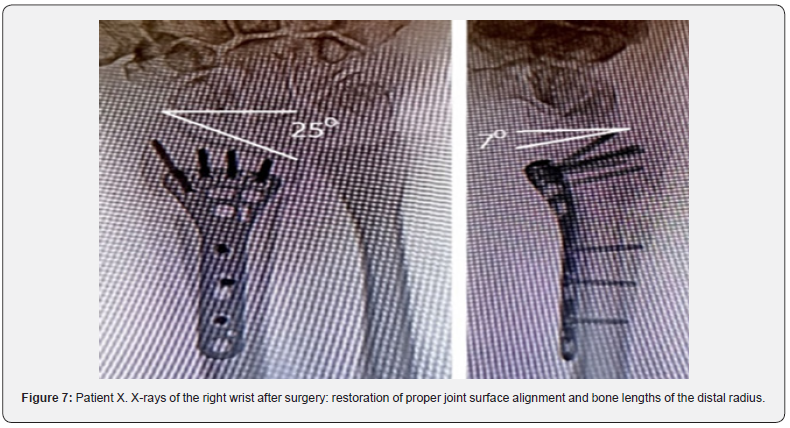

A clinical case. Patient X, a 58-year-old female, presented two months after injury with the diagnosis of a malunited distal radius fracture on the right (AO/ASIF type A 3.2) with delayed carpal tunnel syndrome (DCTS). Upon admission, she complained of wrist deformity, pain, limited range of motion in the right wrist, decreased sensation in fingers 1, 2, and 3, and reduced grip strength. Objectively, the total range of active movements in the right wrist compared to the contralateral limb was 64%, and the gross grip strength was 35%. Pain intensity on the VAS scale reached 4.7 points under load.

X-rays showed angular palmar displacement of the distal radial cortical plate, a reduction in the ulnar-radial angle to 12.3°, an increase in dorsal tilt of the radial joint surface in the sagittal plane to -4° and shortening of the radial bone by 4 mm (Figure 4). Electroneuromyography (ENMG) of the upper extremities revealed a decrease in the M-response of the median nerve at the right wrist (APB-CMAP) and a decrease in sensory conduction velocity of the median nerve (SCV) (Figure 5). According to the classification by A. Żyluk et al. (2014) [25], a severe grade of CTS was diagnosed. The function of the right upper limb on the DASH score was 45.8 points (unsatisfactory). In a planned surgery, from a limited palmar approach to the right wrist, open decompression of the median nerve with epineurotomy and external neurolysis was performed (Figure 6a). Subsequently, through a palmar approach to the forearm, extra-articular open-angle corrective osteotomy and osteosynthesis of the distal radius were performed (Figure 6b).